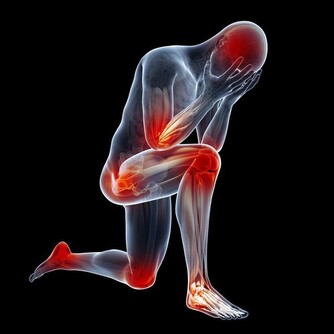

喝酒其實會帶給身體很多不同的負擔,像說高血壓跟增加心臟疾病的可能性。